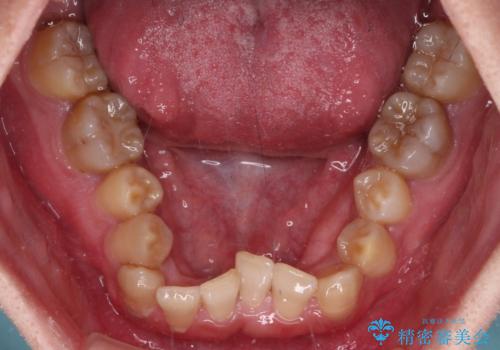

- 上下の前歯のデコボコを改善したいと来院された患者様です。

上顎の歯列幅が狭く、それによって歯が並ぶスペースが不足しています。

また下顎の歯列幅も制限され、内側に歯が倒れています。